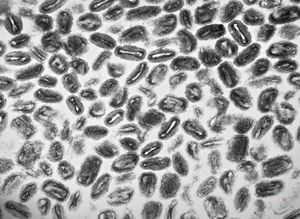

F, 24y. | molluscum contagiosum … virions

F, 24y. | molluscum contagiosum

F, 7y. | molluscum contagiosum … virions